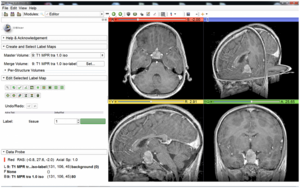

3D Slicer Enabled Research

3D Slicer is a free open source software package distributed under a BSD style license. The majority of funding for the development of 3D slicer comes from a number of grants and contracts from the National Institutes of Health. See Slicer Acknowledgments for more information.

This page focuses on research that was done outside of our immediate collaboration community. That community is represented in the publication database.

We invite you to provide information on how you are using 3D Slicer to produce peer-reviewed research. Information about the scientific impact of this tool is helpful in raising funding for the continued support.